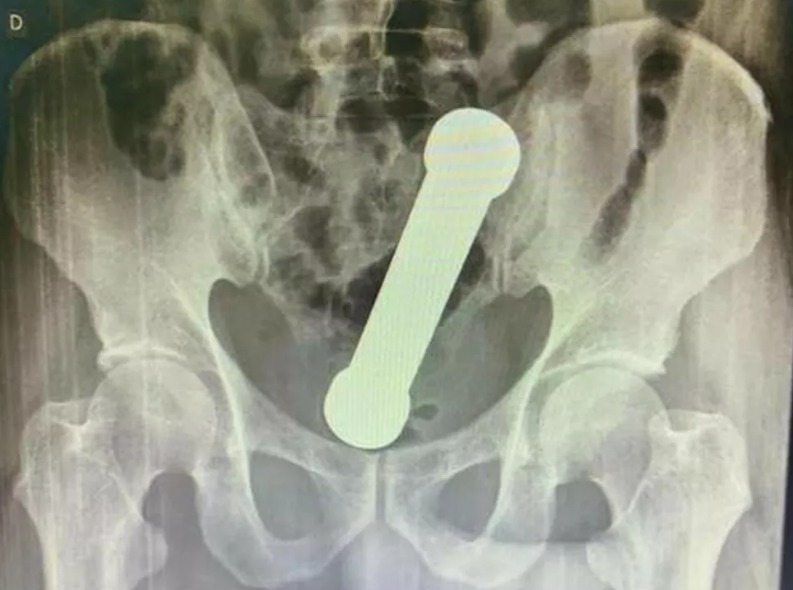

Foto: Reprodução/International Journal of Surgery Case Reports.

De acordo com o estudo, o homem chegou ao hospital com dores abdominais, náuseas, vômitos e outros problemas intestinais. Não havia sinais de perfuração no corpo dele. Os médicos realizaram exames de toque, de sangue e uma radiografia.

A partir do resultado do exame de radiografia, a equipe médica identificou um halter, utilizado em exercícios físicos, próximo ao reto do paciente. O homem então foi encaminhado ao centro cirúrgico e o objeto foi retirado de forma manual.